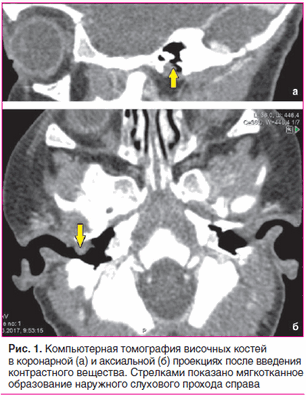

По данным компьютерной томографии височных костей, выполненной по стандартной программе до и после внутривенного введения контрастного вещества, на задней стенке наружного слухового прохода справа определяется мягкотканное образование однородной структуры, овальной формы с четкими контурами, размером 7×5,5 мм. Образование прилежит к барабанной перепонке, несколько смещает ее внутрь, умеренно накапливает контрастный препарат. Просвет наружного слухового прохода в данной области сужен до 1 мм. Костных деструктивных изменений не выявлено. Антрум и барабанные полости с обеих сторон пневматизированы. Слуховые косточки прослеживаются четко. Улитки без особенностей (рис. 1).

После угасания острого воспалительного процесса наружного слухового прохода справа выполнена компьютерная томография височных костей с внутривенным введением контрастного вещества.

С целью уточнения распространенности процесса назначена компьютерная томография височных костей с внутривенным введением контрастного вещества.